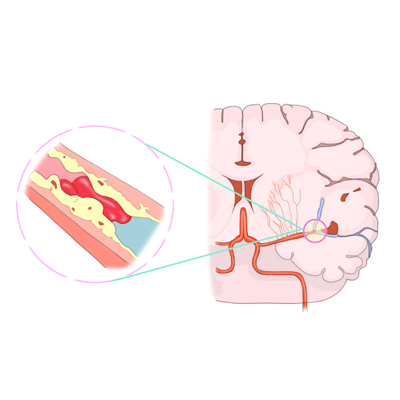

뇌졸중은 크게 두 가지로 나뉘는데요. 혈관이 막혀 뇌의 일부가 손상되는 ‘뇌경색’, 그리고 혈관이 터져 뇌에 출혈이 생기는 ‘뇌출혈’로 구분됩니다. 이 중 뇌경색이 전체 뇌졸중의 약 85%를 차지합니다.